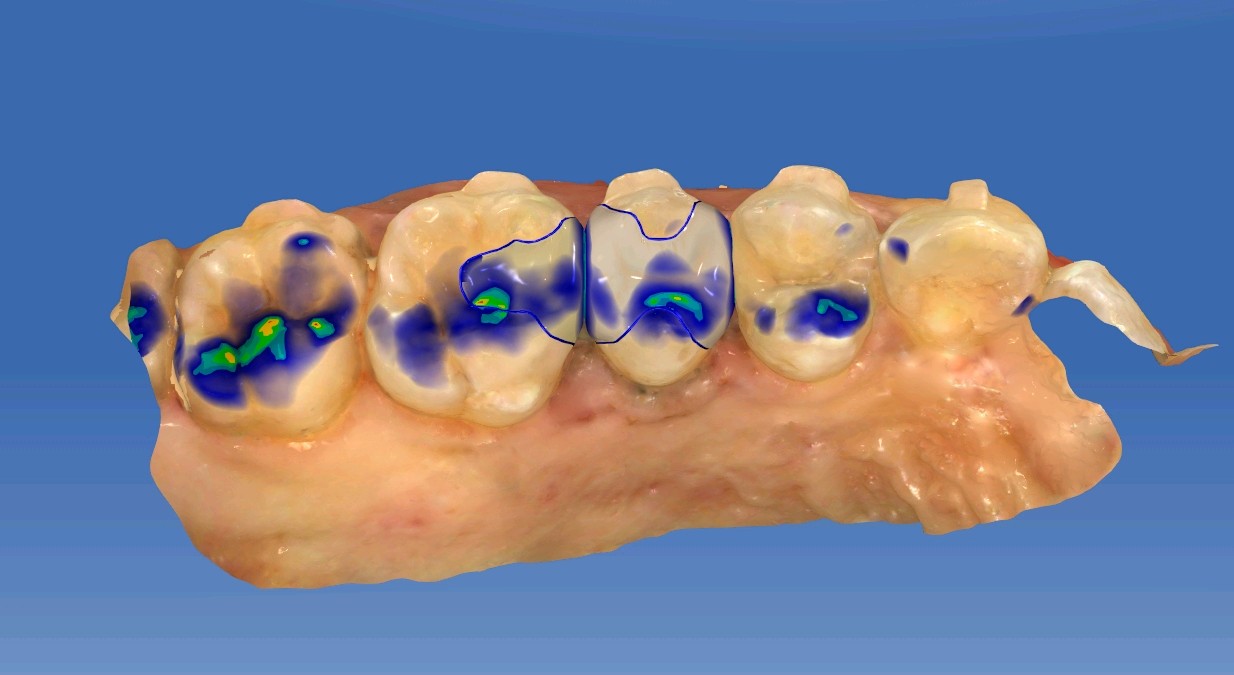

患者女,三十岁,15邻颌面大面积充填物,邻接过紧,食物嵌塞,探(+-),叩(-),冷测试正常,余无不适。很多人牙体缺损面积较大,补牙后很会出现脱落的现象,还有的让选择简单的修复模式补牙,但大量的临床研究显示,牙科树脂充填材料会产生聚合收缩(树脂材料老化),形成微渗漏,引起继发龋(顺着充填材料周围,在牙齿上出现新的腐坏、变黑)。像这种面积比较大的龋齿单纯补牙的话,不耐用。这时候就可以选择嵌体修复。嵌体牙体预备量少,能够保持牙齿外形的完整,减少对牙髓的刺激。还有就是嵌体更耐磨使用寿命较长,从而减轻了患者频繁补牙的痛苦。通过 CEREC 扫描更加精准有效的提高了我们工作效率,当天即可戴牙,正常使用。